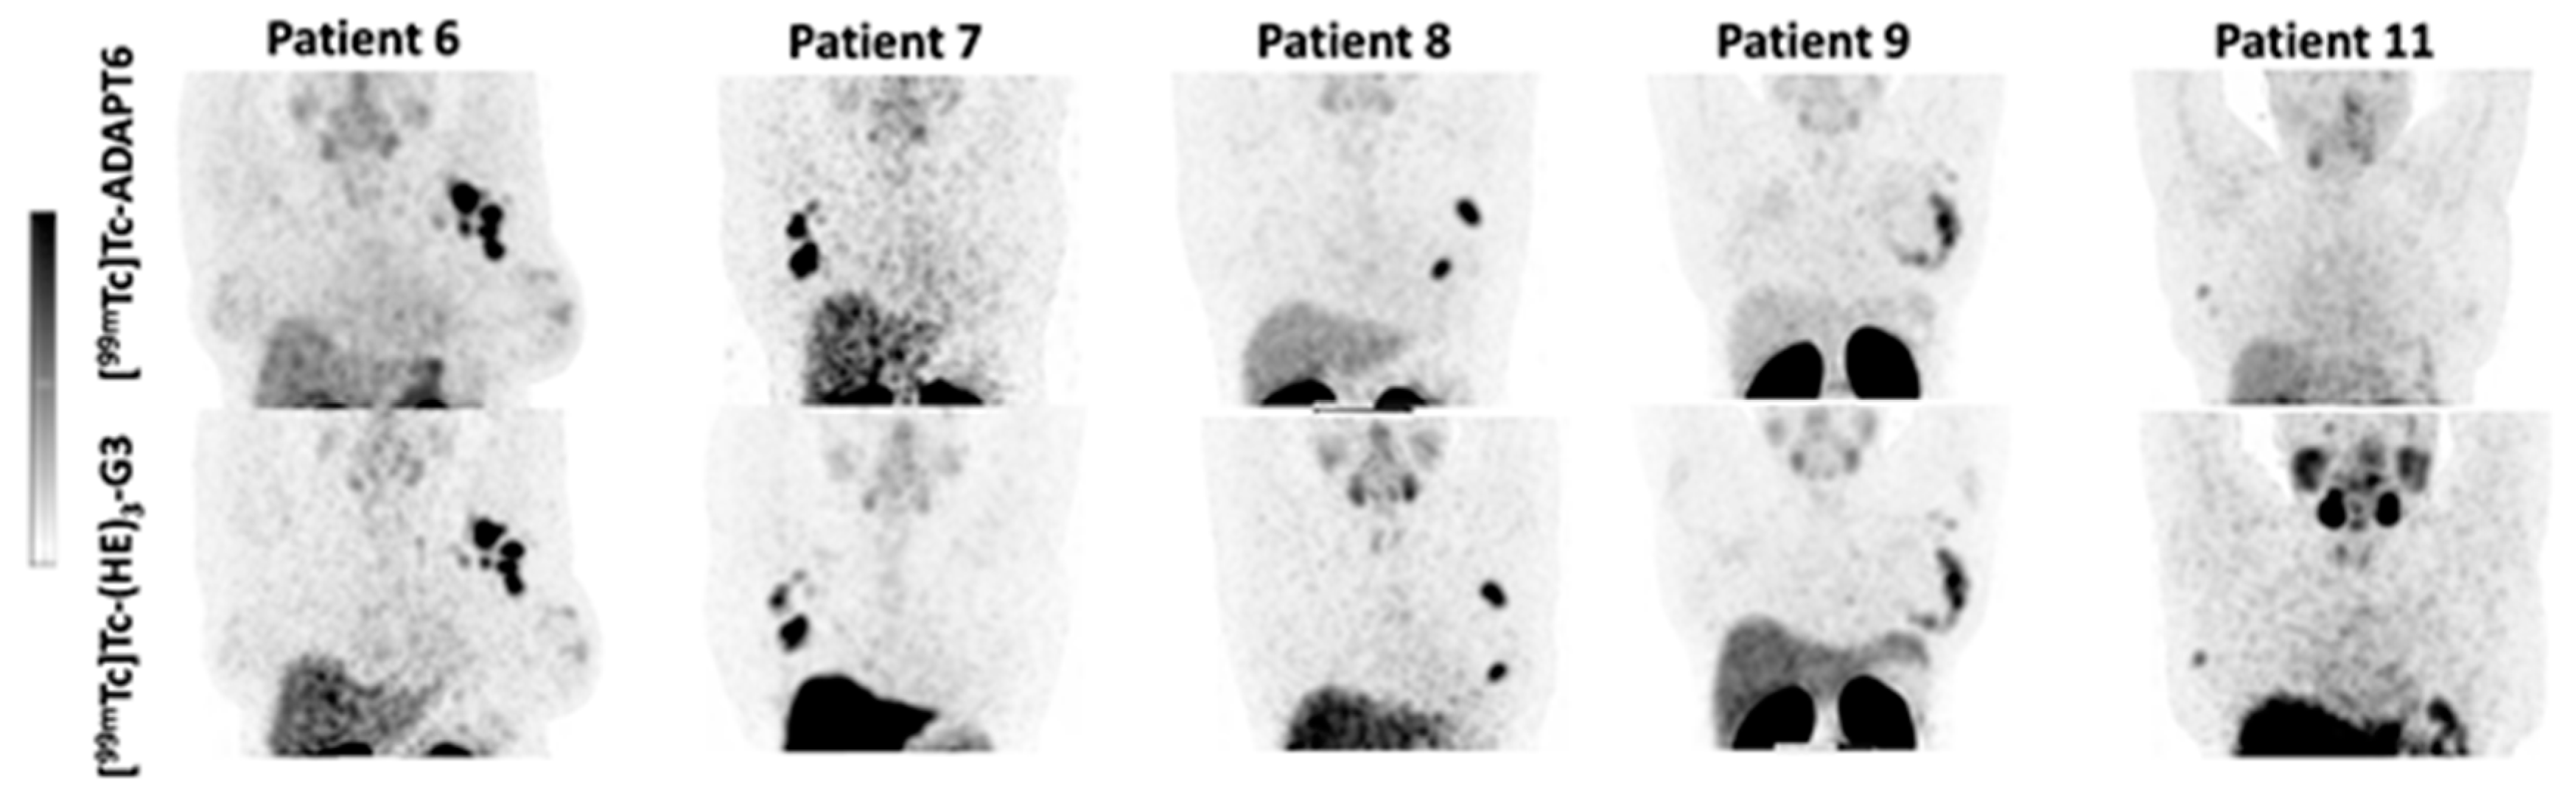

3. Results

4. Discussion